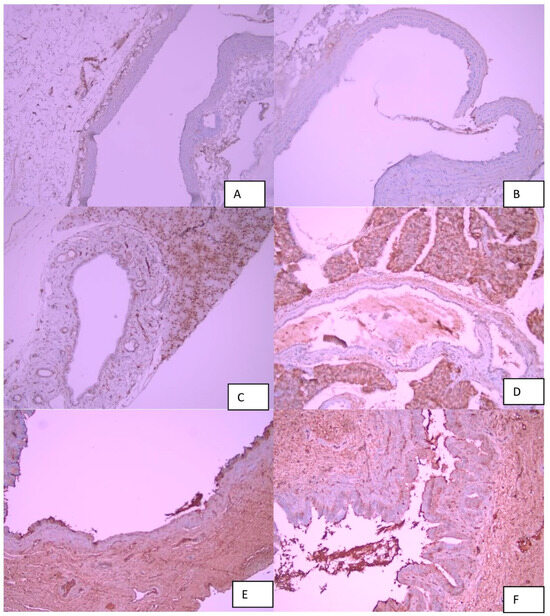

Antifibrotic Effect of the TGF-β Type I Receptor Inhibitor EW-7197 on Anastomotic Healing in a Rat Choledochojejunostomy Model

Biomedicines 2026, 14(3), 698; https://doi.org/10.3390/biomedicines14030698 - 17 Mar 2026

Background/Aim: Anastomotic stricture following choledochojejunostomy (CJS) is largely driven by fibrotic remodeling at the anastomotic site, a process mediated by transforming growth factor-β (TGF-β) signaling. This problem is particularly relevant in emergency biliary surgery, where CJS is frequently performed under suboptimal conditions [...] Read more.

Background/Aim: Anastomotic stricture following choledochojejunostomy (CJS) is largely driven by fibrotic remodeling at the anastomotic site, a process mediated by transforming growth factor-β (TGF-β) signaling. This problem is particularly relevant in emergency biliary surgery, where CJS is frequently performed under suboptimal conditions and anastomotic leakage is common, predisposing to exaggerated fibrosis and late strictures. This study aimed to evaluate the effect of the TGF-β type I receptor (ALK5) inhibitor EW-7197 (vactosertib) on histopathological parameters of anastomotic healing, with a particular focus on fibrosis, in a rat CJS model. Materials and Methods: Twenty-four male Wistar Albino rats were randomized into three groups (n = 8 each): control (G1), CJS only (G2), and CJS plus EW-7197 (G3). EW-7197 was administered as a single intraperitoneal dose (20 mg/kg) immediately after completion of the anastomosis. On postoperative day 21, choledochojejunal anastomotic tissues were harvested and evaluated histologically using hematoxylin–eosin and Masson’s trichrome staining. Edema, hyperemia, inflammation, and fibrosis were graded using a semi-quantitative scoring system, and intergroup comparisons were performed using non-parametric statistical tests. Results: Compared with surgery alone, EW-7197 treatment resulted in a statistically significant reduction in fibrosis severity at the anastomotic site (p < 0.001) and a significant attenuation of hyperemia (p = 0.007). Edema scores showed a downward trend in the EW-7197-treated group but did not reach statistical significance, while inflammation scores did not differ significantly between the surgical groups. Conclusions: In this experimental rat choledochojejunostomy model, administration of the selective ALK5 inhibitor EW-7197 significantly reduced histopathological fibrosis and hyperemia at the anastomotic site on postoperative day 21 without affecting inflammation severity. These findings support the role of the TGF-β/Smad pathway in bilioenteric anastomotic fibrotic remodeling. However, further studies including molecular validation and functional assessments are required to clarify the translational relevance of these results. Full article